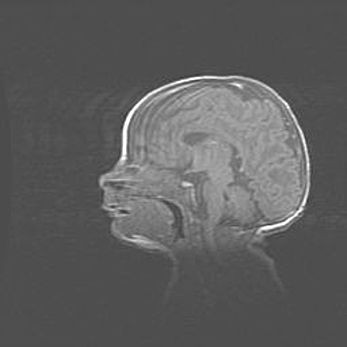

Ниже представлена  галерея МРТ снимков, полученных с применением LMT неонатальных матричных РЧ катушек. Также каждая группа МРТ снимков сопровождается информацией о пациенте (диагноз, возраст, вес, пол, срок гестации) и краткой сопроводительной расшифровкой диагноза.

Аномалия Денди-Уокера. Признаки гипоплазии мозолистого тела.

Возраст: 5 месяцев 3 дня

Вес: 5550 г

Пол: мужской

Окружность головы: 39 см

Срок гестации: 40 недель

Аномалия Денди-Уокера – это порок развития головного мозга, для которого характерна триада симптомов: гипотрофия или аплазия червя мозжечка и/или полушарий мозжечка, расширение четвёртого желудочка с формированием ликворной кисты задней черепной ямки, гипертензионная гидроцефалия различной степени.

Гипоплазия мозолистого тела относится к дефектам внутриутробного этапа развития мозговой ткани, возникающим в процессе закладки структур головного мозга, что происходит на начальных этапах развития эмбриона.